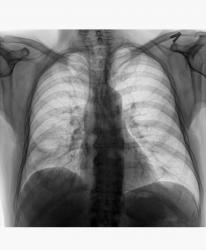

Добрый вечер, Валентин Львович. Я тут тоже немного оклемался от ОРВИ, появились силы выстовить случай. Данная демонстрация немного с подвохом, проанализируйте ещё раз рентгенограммы, более внимательно.

Видна полость напоминающая "абсцесс" справа, но это стандарта исследования не меняет.

Загадка кроется в средостении, а именно в заднем отделе средостения.

Мой коллега после МСКТ-ОГП, решил почему то о наличии фиксированнай грыжи диафрагмы, пациент попал ко мне на R-скопию пищевода и желудка:

Пациент поступил в стационар(отеделение терапии) с Ds: Внегоспитальной правосторонней пневмонией. После того как мой коллега описал при поступлении цифровые R-граммы ОГП, отметив о наличие фиксированной грыжи пищеводного отверстия дифарагмы(под вопросом), клиницисты сразу направили пациента на КТ с предворительным обоснованием: пневмония, абсцесс, ГПОД? И только спустя через 3-4 дня после МСКТ, как только пациент был прокунсультирован хирургом, его направили ко мне на R-скопическое исследование. МСКТ-делалось только один раз.